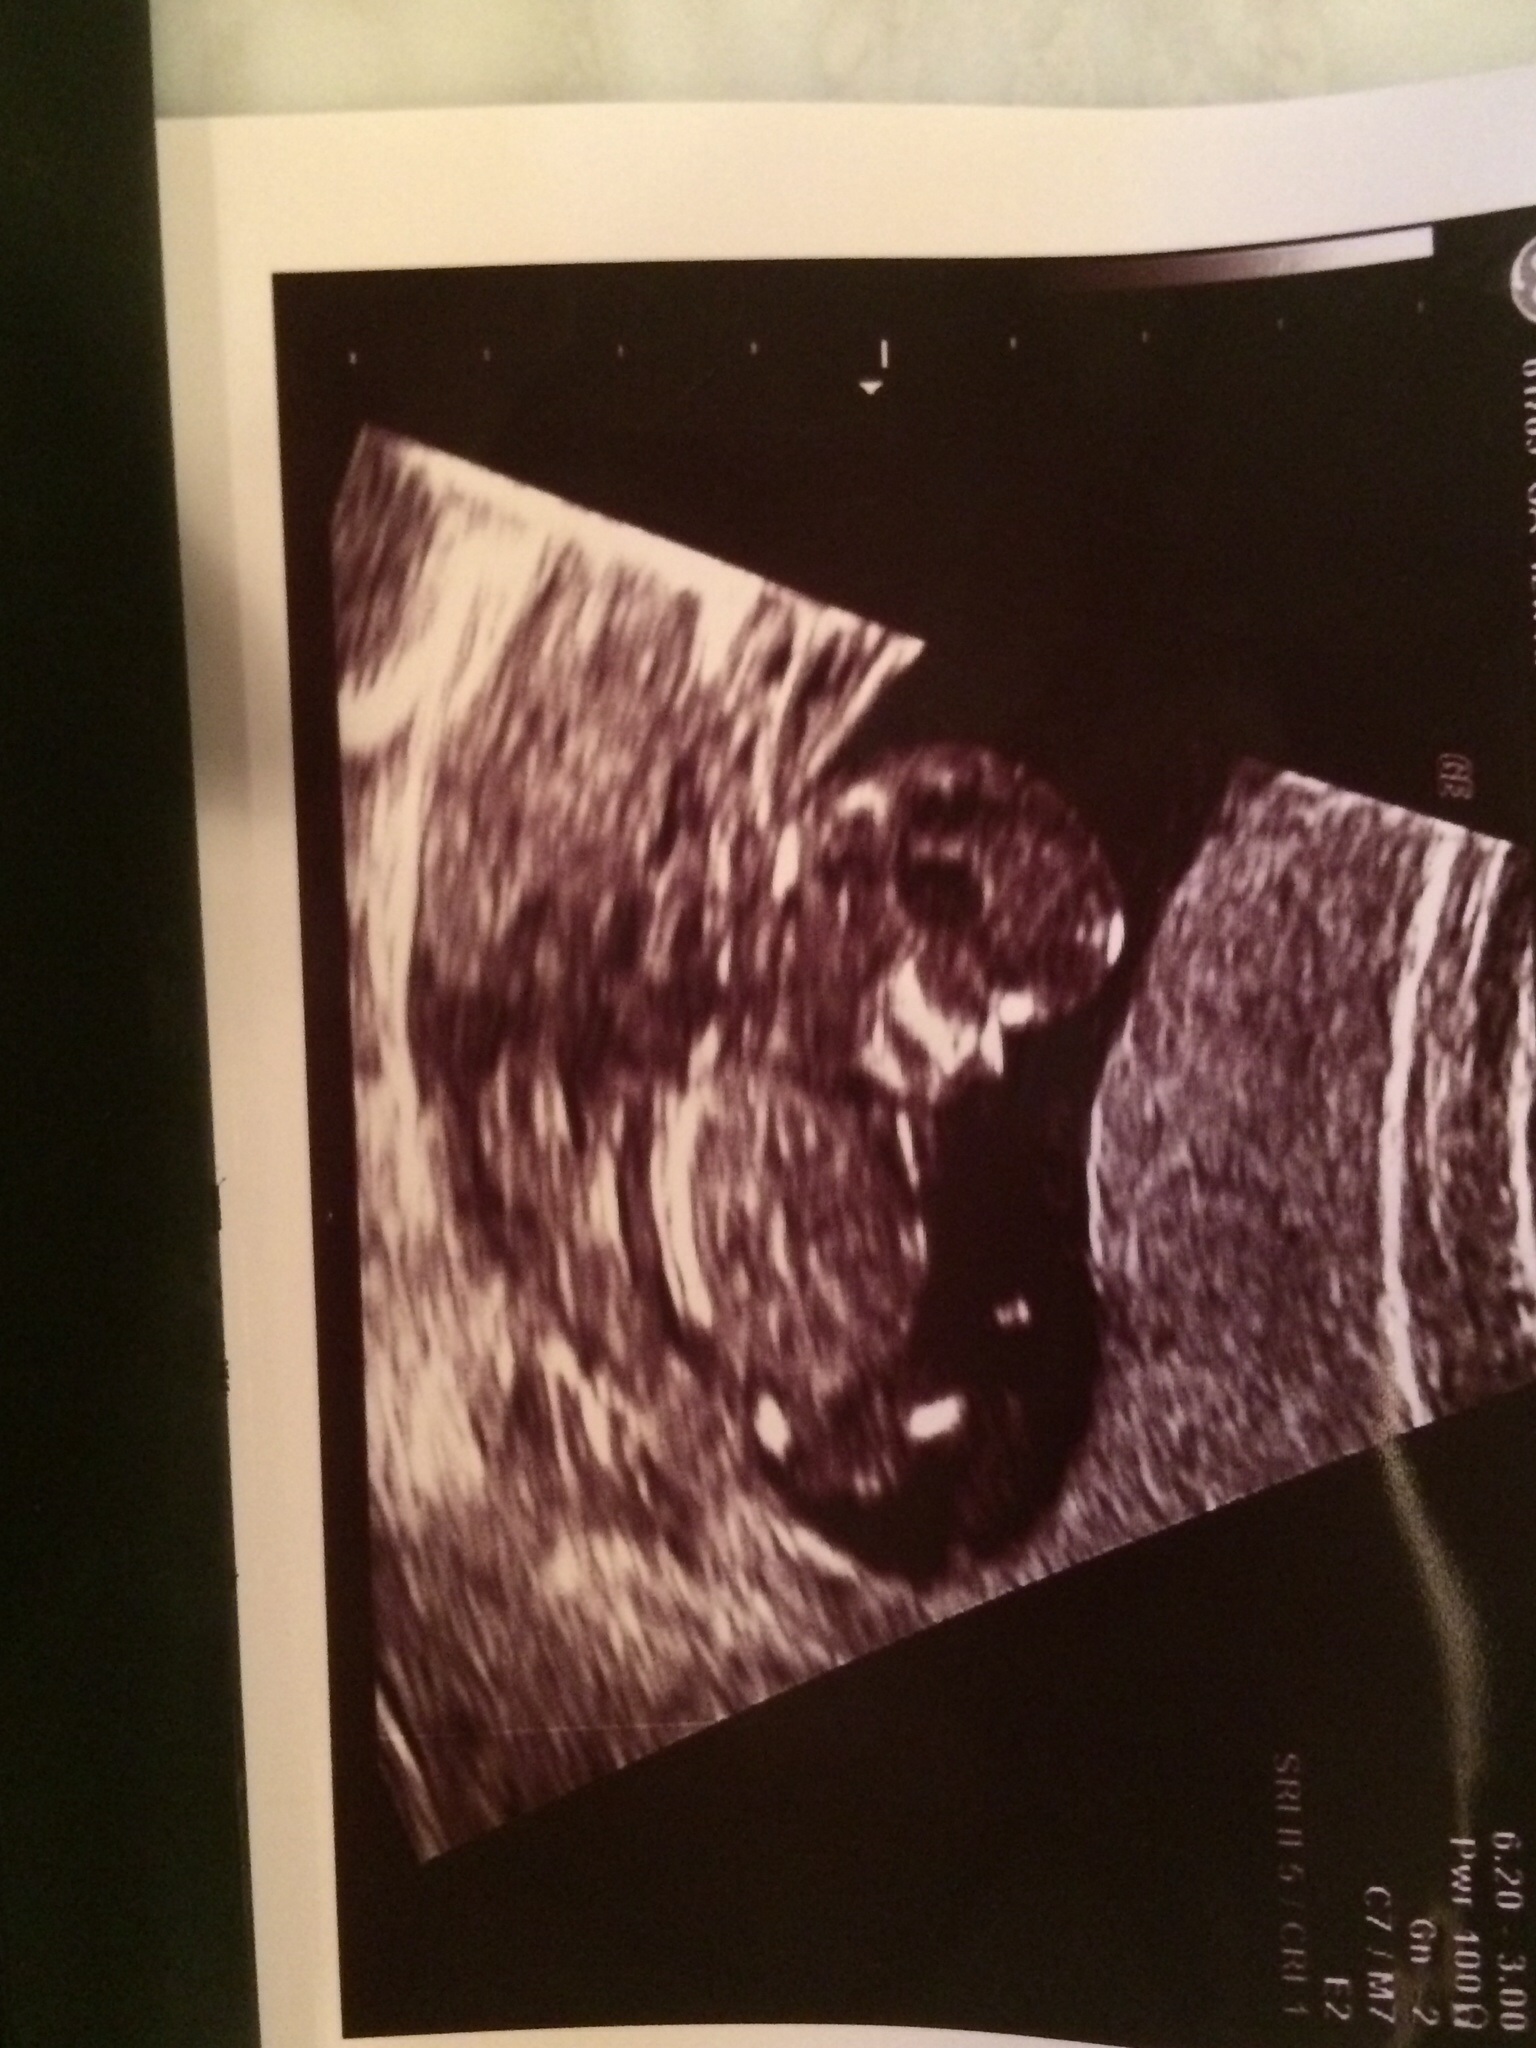

Attachment 20083 Attachment 20084 Pic taken 12w 4 days